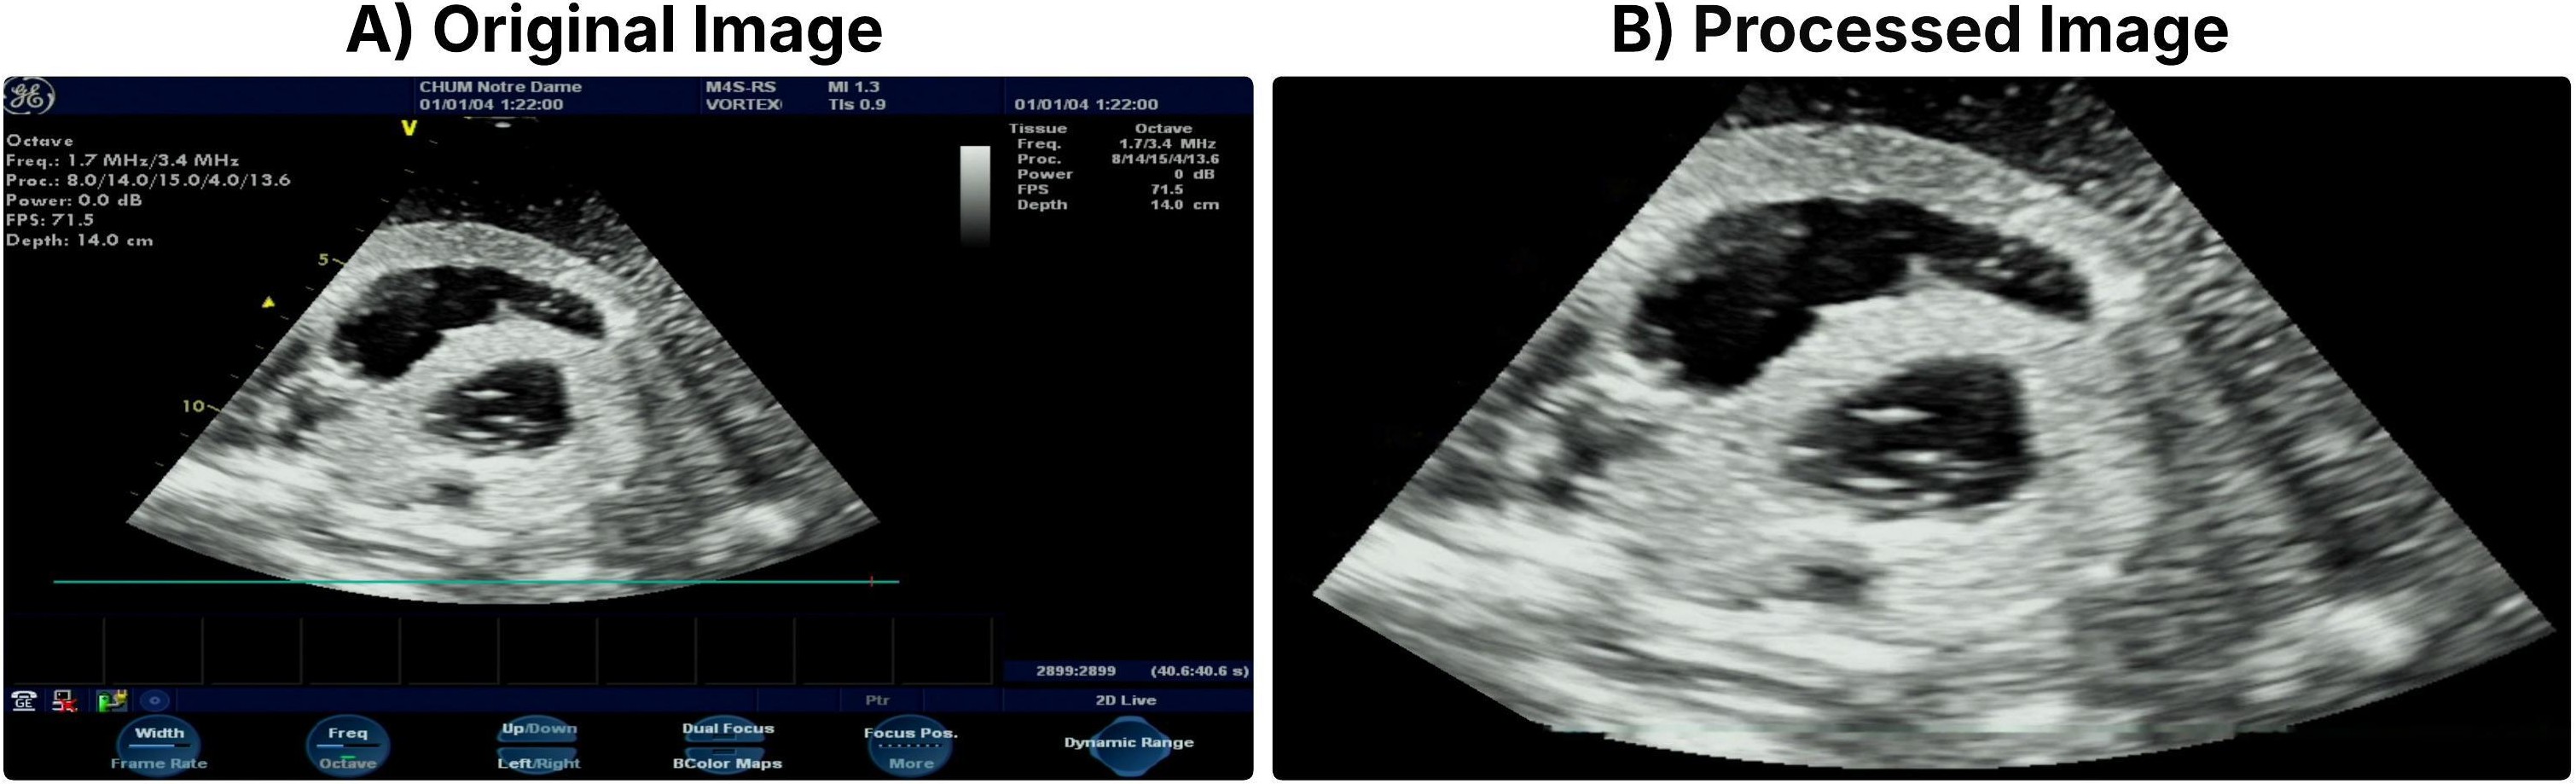

Refer to caption

Figure 1: A) Original ultrasound frame with overlay annotations. B) Cropped and cleaned, processed and inpainted image used for analysis.

Ultrasound images often contain sector-shaped acquisition regions and colour annotations or markers, as shown in Fig. 1A. To standardize the input and reduce irrelevant visual artifacts, we applied a three-stage preprocessing pipeline.

Sector masking and cropping. Each image was first converted to RGB, and a sector mask was applied to isolate the ultrasound field of view. The mask was defined using a pie-slice geometry centred at the bottom midpoint of the image with angular limits of 210210^{\circ} to 330330^{\circ} and radius equal to 90% of the image height. Pixels outside this region were set to zero. The masked image was then cropped using fixed bounding coordinates to remove peripheral borders and scanner overlays.

Annotation mask extraction. To remove embedded colour annotations, images were converted to the HSV colour space. Colour thresholds were applied to detect yellow, blue, and red overlays commonly used for measurement markers. Binary masks were generated using these thresholds and subsequently dilated with a 5×55\times 5 kernel to ensure complete coverage of annotation regions.

Inpainting. Detected annotation regions were removed and filled in the missing pixel values using the Navier–Stokes–based inpainting [17] implemented in OpenCV (Fig. 1B). This step ensured that classification performance reflected anatomical content rather than overlaid measurement graphics or noisy artifacts.